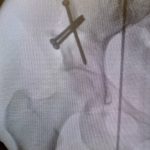

J’ai récemment expérimenté la chirurgie de prothèse de genou assistée par bras robotisé.

- Cette technologie permet une grande précision dans l’équilibrage ligamentaire du genou, essentiel pour retrouver une articulation stable et souple.

- Elle facilite également le choix de la taille et de la forme de l’implant en fonction de chaque morphologie, pour un résultat sur mesure.